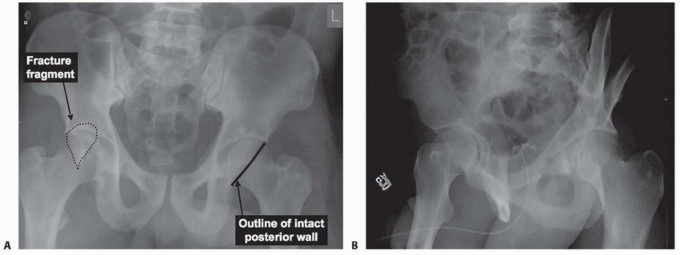

n DEFINITION A posterior wall fracture is one of the elementary fracture types as described by Letournel and …